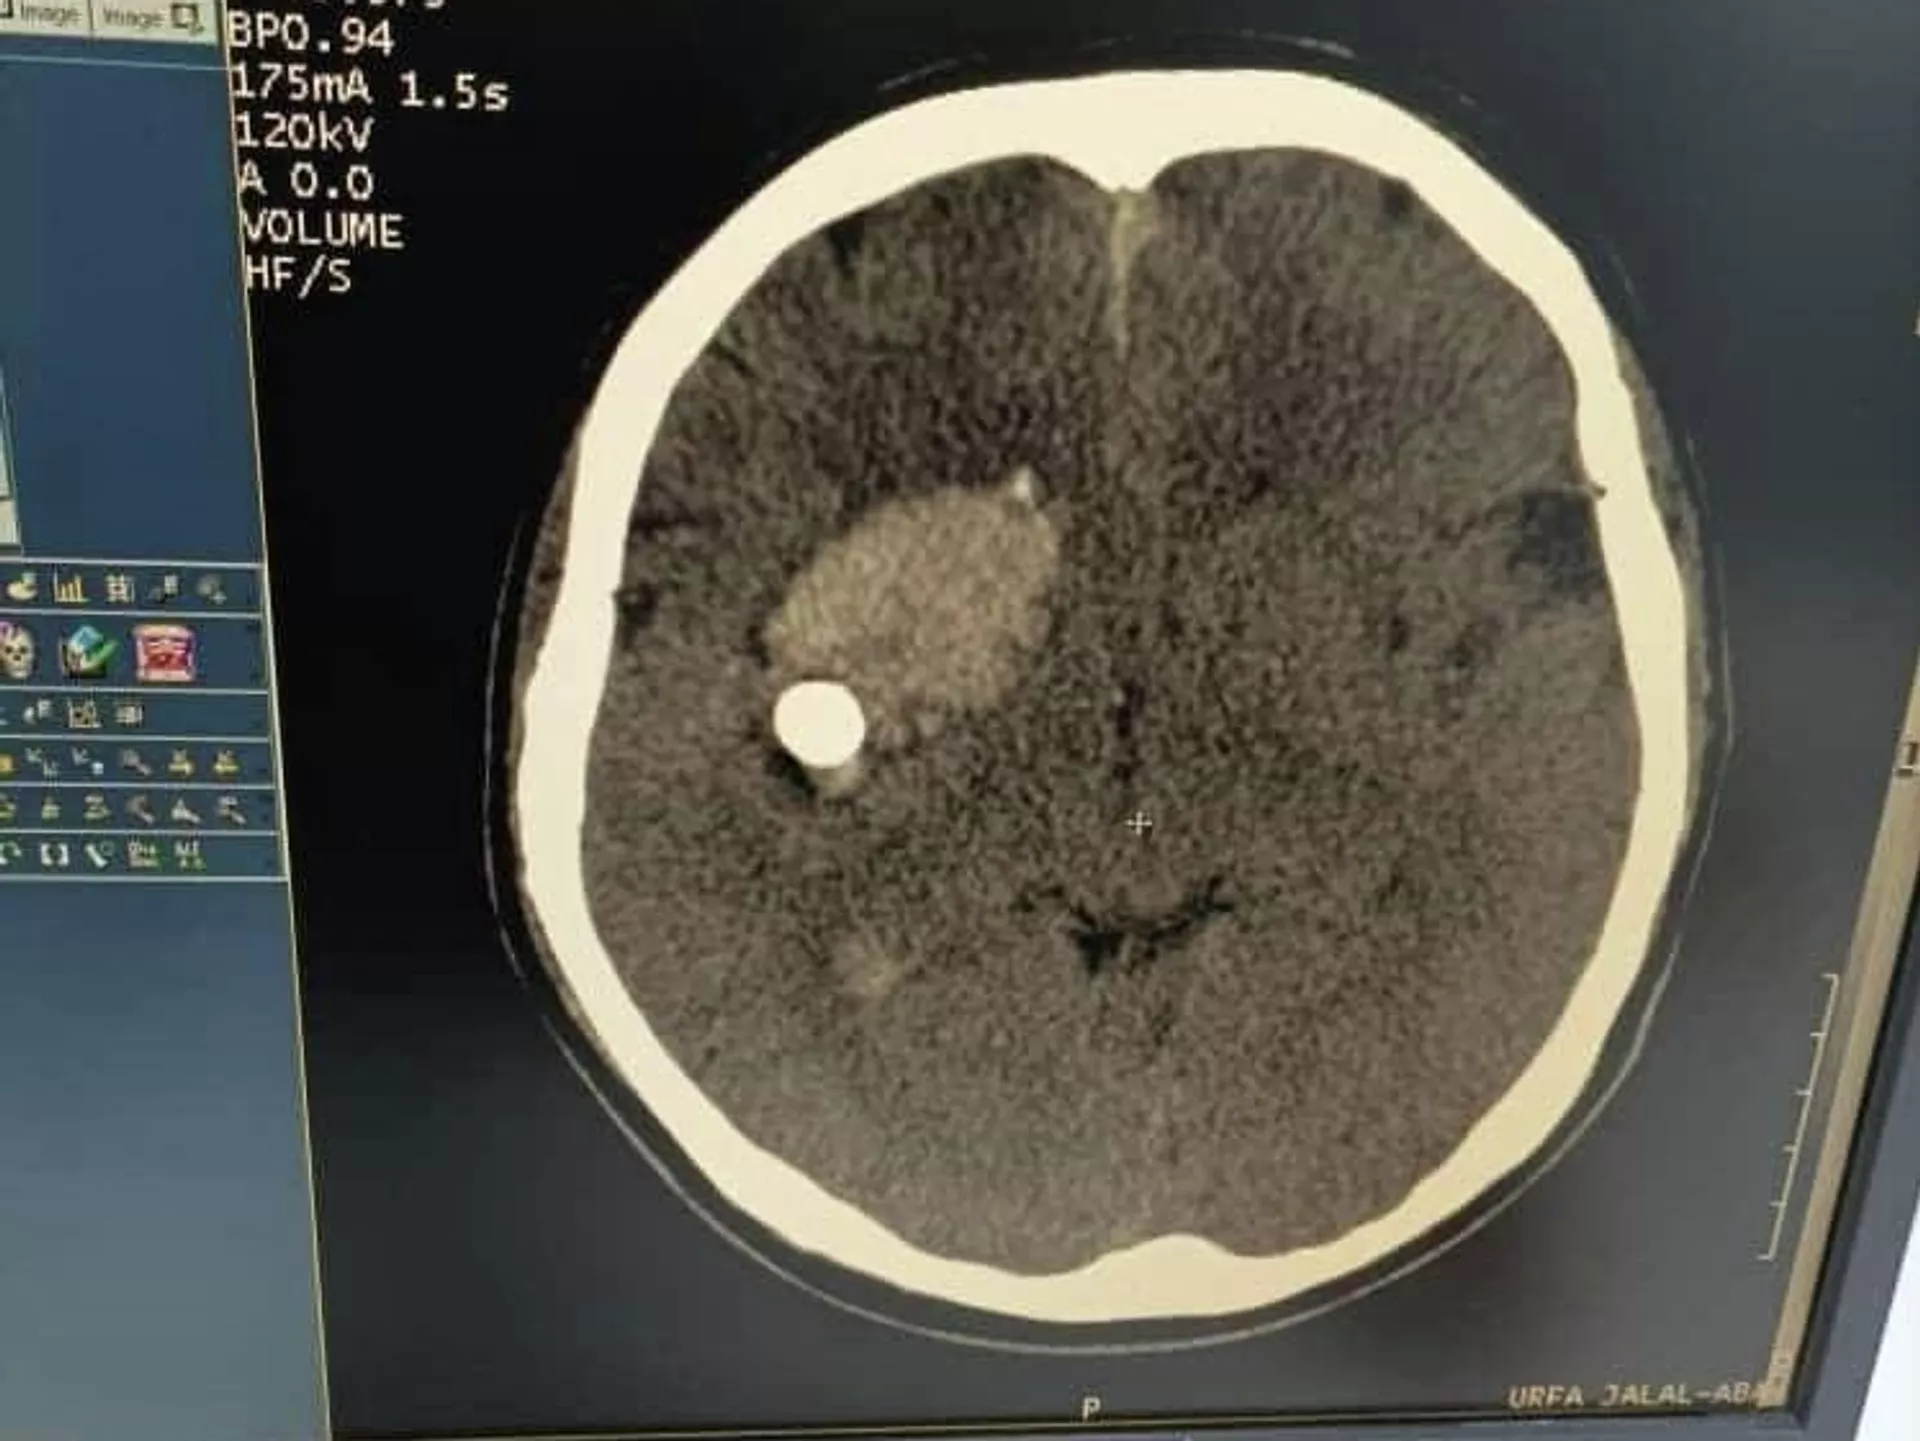

БИШКЕК, 10 фев — Sputnik. Кыргызстанские врачи успешно прооперировали пациента с пулей в голове.

Сложную операцию на мозге провели в Джалал-Абадской областной больнице

Как сообщила пресс-служба Министерства здравоохранения, сложную операцию на мозге провели вчера в Джалал-Абадской областной больнице. Пациента спасли заведующий нейрохирургическим отделением Абдибайит Идирисов и его команда. Сейчас состояние пострадавшего стабильное.

В Минздраве сообщили, что мужчина поступил с открытым пулевым ранением головы. Кто в него стрелял, пока неизвестно.